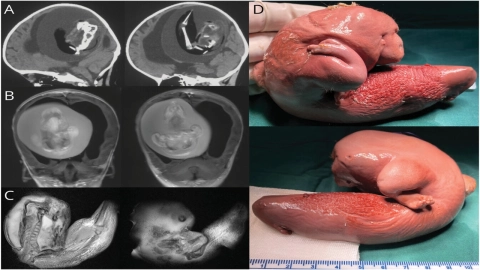

La pequeña paciente, que presentaba retraso motor y un aumento en la circunferencia de la cabeza, fue sometida a una tomografía computarizada y una resonancia magnética que revelaron la presencia de una masa anormal en su interior. Tras una compleja cirugía, los médicos lograron extraer la masa, que resultó ser un feto con columna vertebral, fémur, tibia y extremidades superiores en desarrollo.

En primer lugar, este feto en feto se descubrió "dentro de un saco similar al amnios en el ventrículo del niño anfitrión, lo que proporciona evidencia de una gemelación monocoriónica-diamniótica. Esto difiere de los gemelos unidos, que suelen ser monocoriónicos-monoamnióticos".

Los análisis genéticos posteriores confirmaron que la niña y el feto malformado eran gemelos monocigóticos, es decir, que provenían del mismo óvulo fecundado. Sin embargo, a diferencia de los gemelos comunes, este caso se caracterizó por una separación incompleta de los embriones durante las primeras etapas del desarrollo.